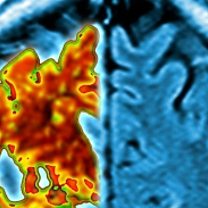

(Picture: Brain scan of a dementia sufferer. Credit: Getty Images)